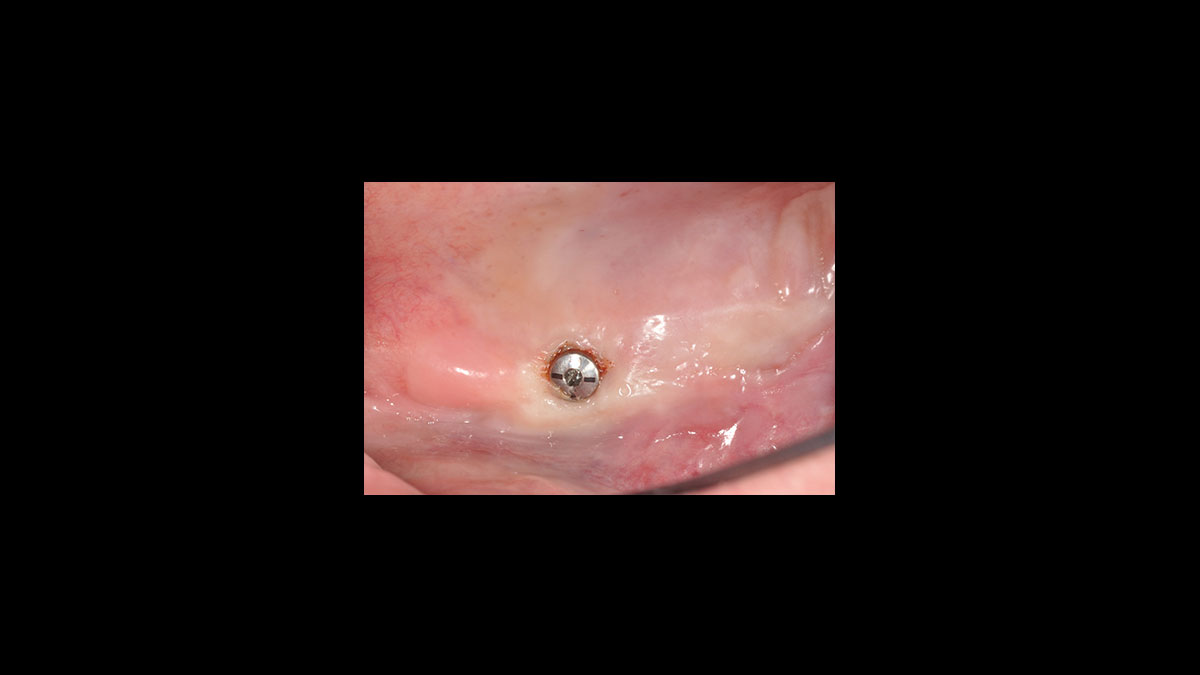

• Implant uncovery

Implant uncovery